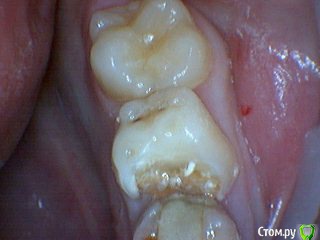

Давлетшин Опубликовано 29 декабря, 2017 Поделиться Опубликовано 29 декабря, 2017 (изменено) Друзья. Расскажите, не поменялось ли ваше отношение к пульпотеку и пр.Почему пломбы поверх пульпотеку такие ужасно жёлтые? Что сделать можно. Или что я делаю не так? "Друзья" так приятно перед новым годом. К пульпотеку не поменялось (устраивает вполне) , к пульподенту скептическое отношение, хоть и тоже работаю. Пломбы сразу желтые или через полгода - год- два? Очень тяжело что то советовать он лайн не видя как человек работает. В фото первая цифра пациент, вторая-третья номер зуба, четвертая порядок фото. Я после наложения пульпотека , стараюсь убрать излишки, или аккуратно на устья каналов накладываю, в пульповую камеру СИЦ, и сверху пломбу, Убрать излишки и со стенок, аккуратно в том числе и бором. В третьем клиническом случае, неудача. Зуб удалил сам же через 3 месяца. причину вижу в том что на рентгене не увидел (или так сделали снимок?) вертикальный тип рассасывания практически до бифуркации., может и потому что ребенок ОЧЕНЬ плохо сидел. За фото не пинайте сильно, не инстаграмм все таки,да и тяжело ребенка лечить и фотки делать. или наоборот пинайте может лучше начнем фоткать. P.s. Добавлю протокол как лечу с пульпотеком, хр.фибр.пульпит1. анестезия2. кофер ( если дает)3. раскрытие кариозной и пульповой камеры4. удаление коронковой пульпы маленьким эскаватором, я стараюсь "отрубать" пульпу5. остановка кровотечения сухим ватным шариком, 0,5-1-2 минуты6. пульпотек на устья7 СИЦ в пульповую камеру8 со стенок остатки пульпотека соскребаю бором фиссурным , цилиндрическим, там же фальц9. Пломба. может что то и зыбыл ну и оценка только позитивная перед НГ Изменено 29 декабря, 2017 пользователем Давлетшин 2 Ссылка на комментарий